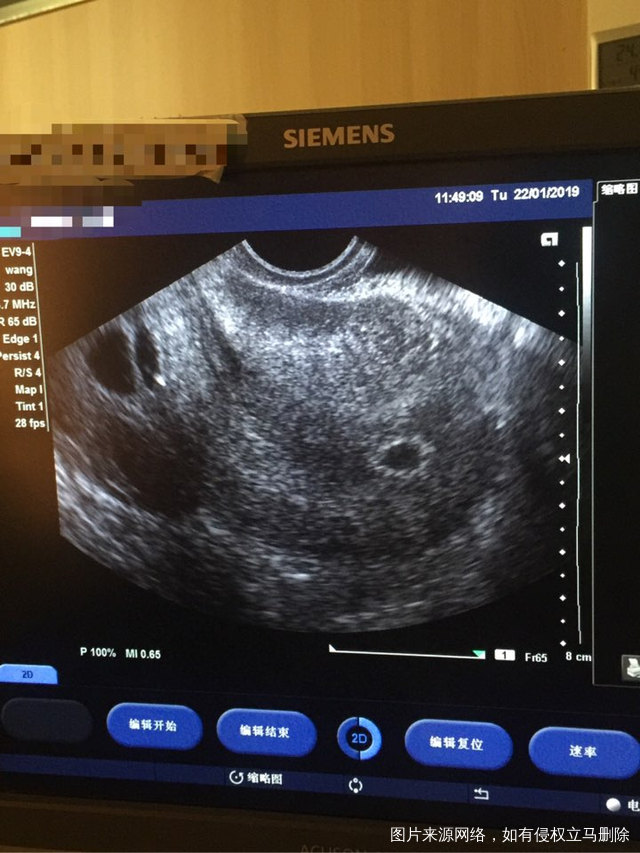

宝宝你要保佑妈妈啊,最后一个星期了